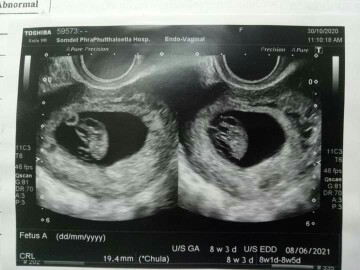

8มิ.ย64จ้า 10วีค